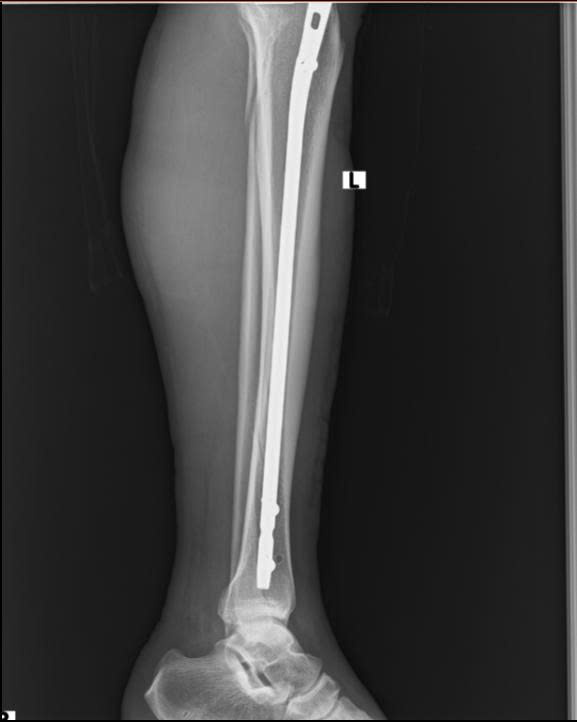

Đột phá mới trong điều trị gãy xương cẳng chân tại Bệnh viện Đa khoa Hòa Bình Kỹ thuật đóng đinh nội tủy có chốt ngang dưới màn tăng sáng – Ít xâm lấn, hiệu quả vượt trội

Trong lĩnh vực chấn thương chỉnh hình, điều trị gãy hai xương cẳng chân luôn là một thách thức lớn, đòi hỏi kỹ thuật cao và khả năng phục hồi nhanh để giảm ...